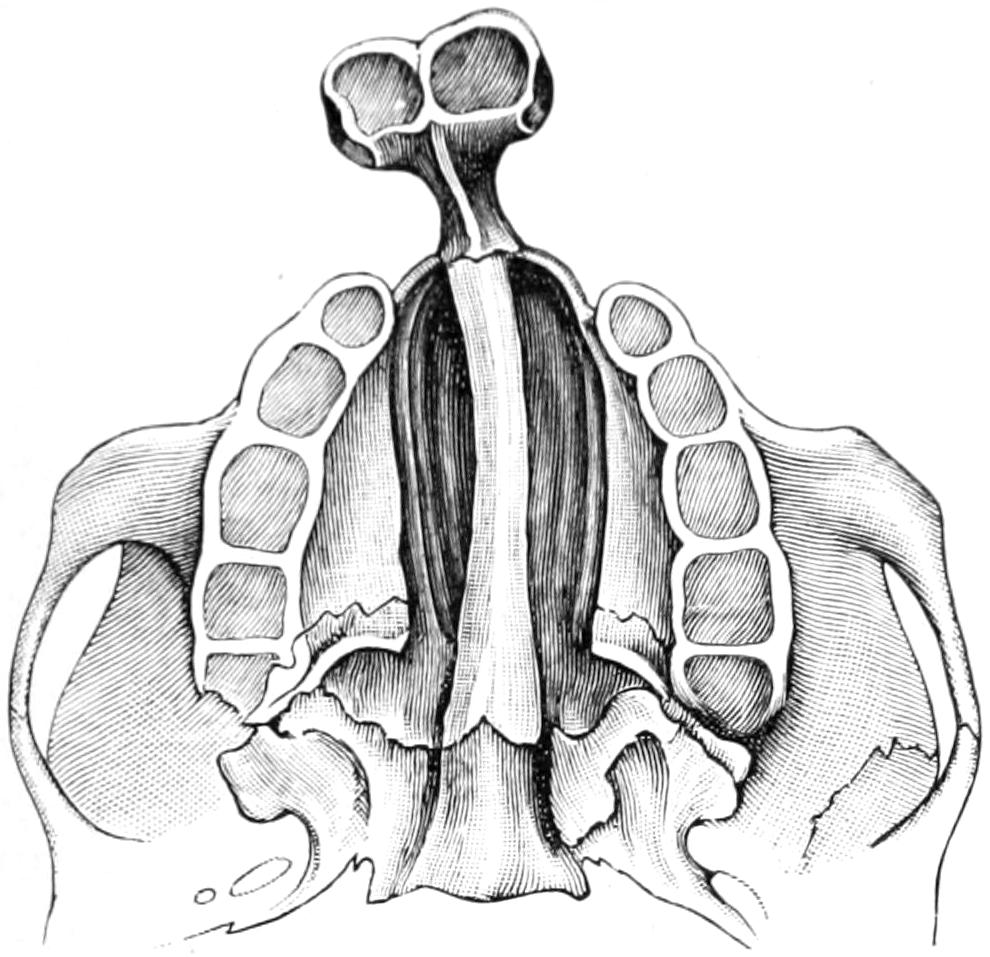

PLATE I

Fig. I.

Fig. II.

Fig. III.

Fig. IV.

Fig. V.

Fig. VI.

Fig. VII.

Fig. VIII.

DRAWN BY J. N. Z. CHASE

PLATE I.

BLOOD.

(Ehrlich triple stain.)

(Prepared by Dr. I. P. Lyon.)

Fig. I. TYPES OF LEUCOCYTES.

a. Polymorphonuclear Neutrophile. b. Polymorphonuclear Eosinophile. c. Myelocyte (Neutrophilic). d. Eosinophilic Myelocyte. e. Large Lymphocyte (large Mononuclear). f. Small Lymphocyte (small Mononuclear).

Fig. II. NORMAL BLOOD.

Field contains one neutrophile. Reds are normal.

Fig. III. ANÆMIA, POST-OPERATIVE (secondary).

The reds are fewer than normal, and are deficient in hæmoglobin and somewhat irregular in form. One normoblast is seen in the field, and two neutrophiles and one small lymphocyte, showing a marked post-hæmorrhagic anæmia, with leucocytosis.

Fig. IV. LEUCOCYTOSIS, INFLAMMATORY.

The reds are normal. A marked leucocytosis is shown, with five neutrophiles and one small lymphocyte. This illustration may also serve the purpose of showing the leucocytosis of malignant tumor.

Fig. V. TRICHINOSIS.

A marked leucocytosis is shown, consisting of an eosinophilia.

Fig. VI. LYMPHATIC LEUKÆMIA.

Slight anæmia. A large relative and absolute increase of the lymphocytes (chiefly the small lymphocytes) is shown.

Fig. VII. SPLENO-MYELOGENOUS LEUKÆMIA.

The reds show a secondary anæmia. Two normoblasts are shown. The leucocytosis is massive. Twenty leucocytes are shown, consisting of nine neutrophiles, seven myelocytes, two small lymphocytes, one eosinophile (polymorphonuclear) and one eosinophilic myelocyte. Note the polymorphous condition of the leucocytes, i. e., their variations from the typical in size and form.

Fig. VIII. VARIETIES OF RED CORPUSCLES.

a. Normal Red Corpuscle (normocyte). b, c. Anæmic Red Corpuscles. d-g. Poikilocytes. h. Microcyte. i. Megalocyte. j-n. Nucleated Red Corpuscles. j, k. Normoblasts. l. Microblast. m, n. Megaloblasts.

The value of a careful blood examination is well illustrated by Plate I, prepared by Dr. Irving P. Lyon, in which are displayed the alterations of greatest interest to the surgeon.